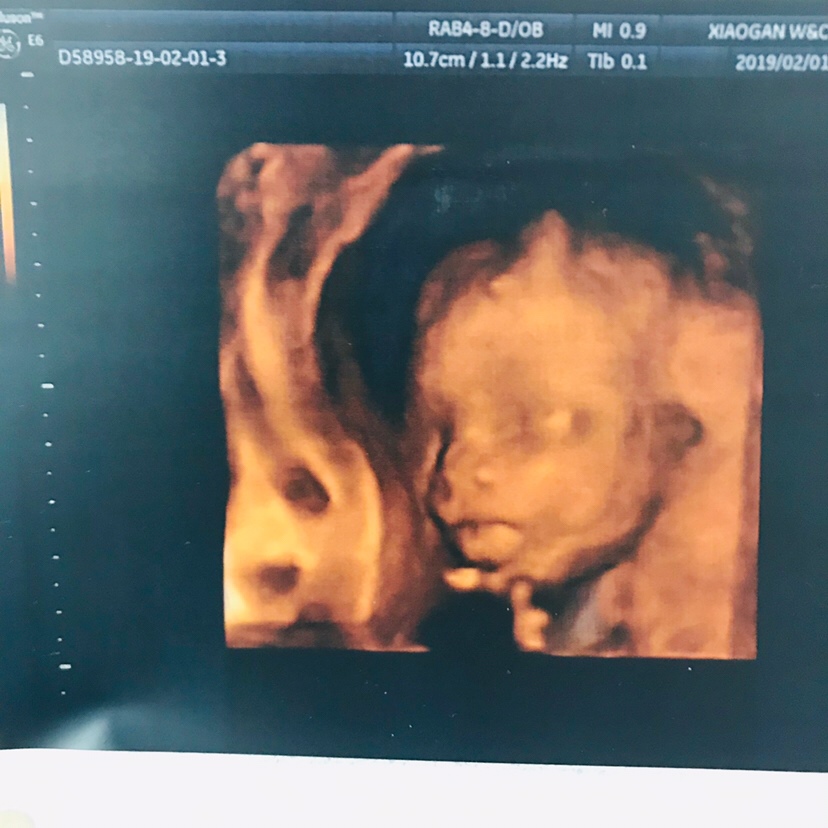

孕18周+4天

我也是二胎,昨天做的这个,挺顺利的,十分钟不到就做完了,医生说你这个月份的今天我是做的最顺利的一个,就是市妇幼的人也是太多了,我的妈呀,每次去都得等2-3个小时才排到,下次做24周的,不知道能不能这么配合了!